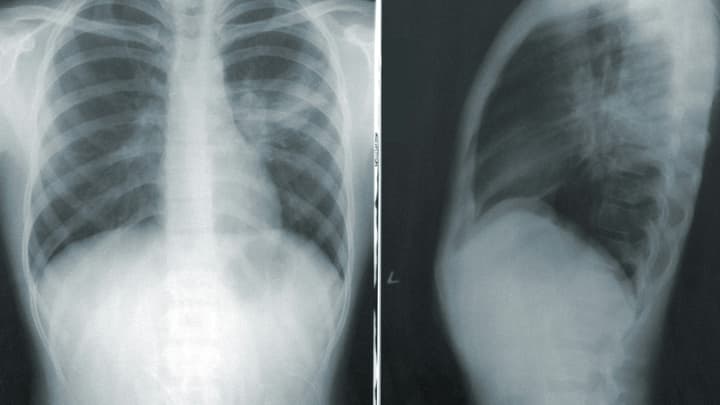

W diagnostyce krwiaka nadtwardówkowego pomocna jest głównie tomografia komputerowa głowy. Pozwala ona na zlokalizowanie ogniska krwiaka. Ma on kształt soczewkowaty i jego gęstość odpowiada gęstości krwi. Czasem widać szczelinę złamania kości czaszki.